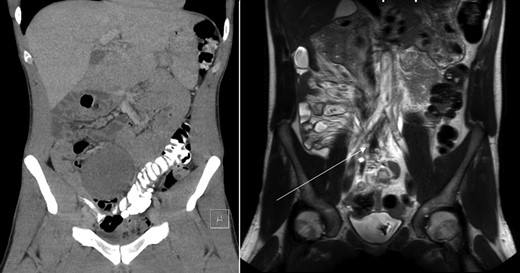

Coronal view of CT-abdomen (left) and MRI-abdomen 1 year later. The lesion has regressed significantly (arrow).

Sonography after three months showed a reduction in size to 9.4 × 5.4 cm2. On request of the patient, who was anxious of having a tumor which was treated conservatively, a second opinion was performed at an University Medical Center. They acknowledged the conservative approach and advised follow up with magnetic resonance imaging (MRI) 1 year after diagnosis. This MRI showed regression of the tumor with a small residue of 2.2 × 1.2 × 1.9 cm2 (Figs 1 and 2) along the right ureter and a minimal hydronephrosis of the right kidney without loss of renal function. A second MRI 6 months later and a third MRI 1 year later showed persisted regression without hydronephrosis. Both scans showed no other masses. The patient did not develop any symptoms during follow up.